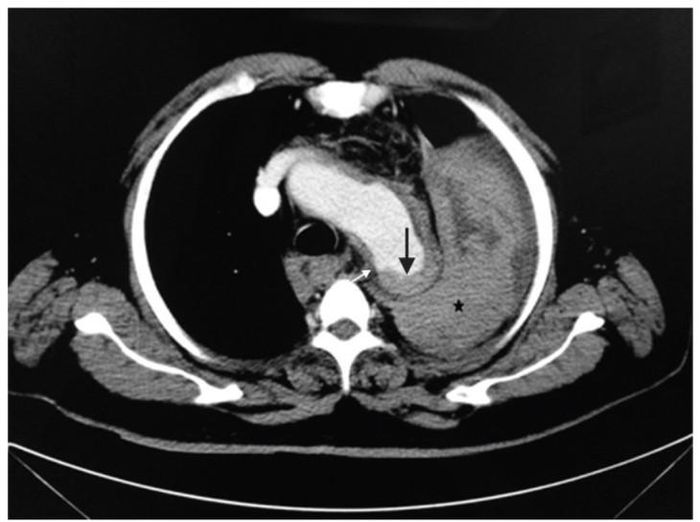

Ngày hôm sau, bệnh nhân bất ngờ hôn mê sau khi hắt hơi. Bác sĩ kiểm tra qua chụp CT xác định vỡ túi phình động mạch chủ khiến người bệnh shock và tử vong ngay sau đó.

Kết quả chụp CT cho thấy bệnh nhân bị vỡ phình động mạch chủ. Ảnh BSCC